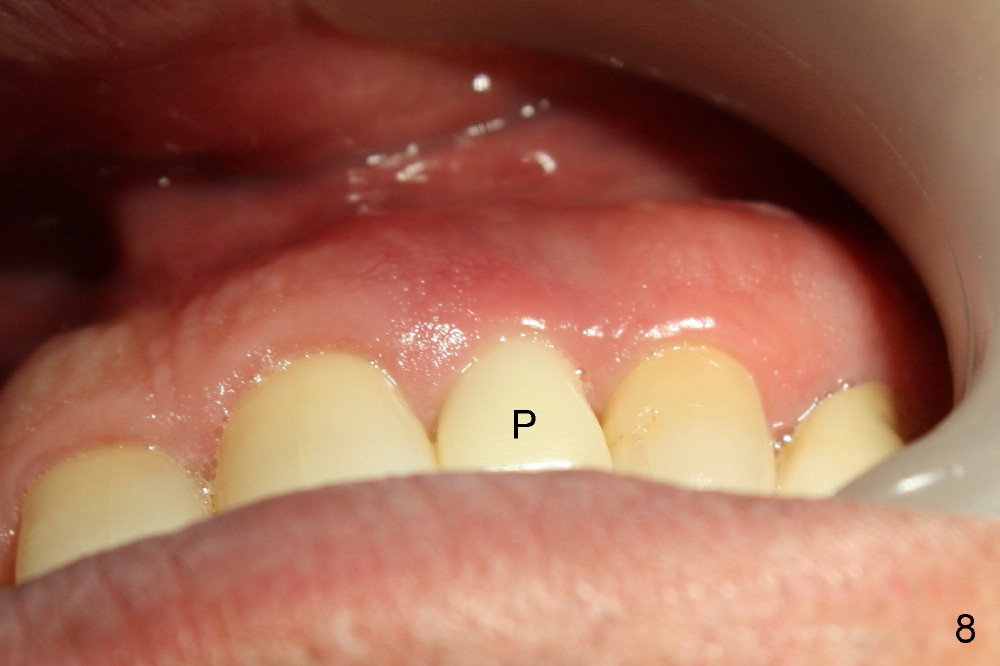

6. Provisional keeps papillae in place